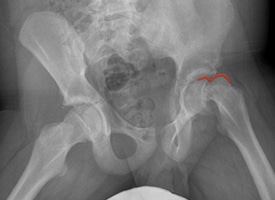

PRE OP

The red line demonstrates a large residual CAM deformity after in situ screw fixation of Slipped Capital Femoral Epiphysis (SCFE). This deformity limits range of motion and impinges against the hip socket causing damage to the joint.